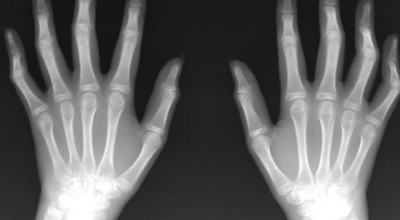

관절염은 크게 ‘퇴행성 관절염’과 ‘류마티스 관절염’으로 나눌 수 있습니다. 퇴행성 관절염은 손가락 관절의 연골이 닳아 뼈끼리 부딪히면서 마디가 튀어나오는 반면, 류마티스 관절염은 염증으로 손가락 마디가 붓고 튀어나오기 때문에 손 모양만으로는 정확히 구분하기 어렵습니다.

류마티스 관절염은 관절을 감싸는 활막에 만성 염증이 생겨 두꺼워지고, 관절 연골과 뼈가 손상되며 기능이 파괴되고 모양이 변형되는 질환입니다. 관절 증상뿐 아니라 빈혈, 미열, 전신 권태감과 함께 심장, 골다공증, 혈관염 등 다른 장기에도 영향을 줄 수 있습니다.

염증이 심해지면 관절 마디에 액체가 차거나 관절 조직이 증식하면서 마디가 부어오르게 됩니다. 염증이 계속되면 주변 근육과 인대도 약화되거나 손상될 수 있어, 손가락이 비틀리거나 변형되어 제대로 기능하기 어려워집니다.